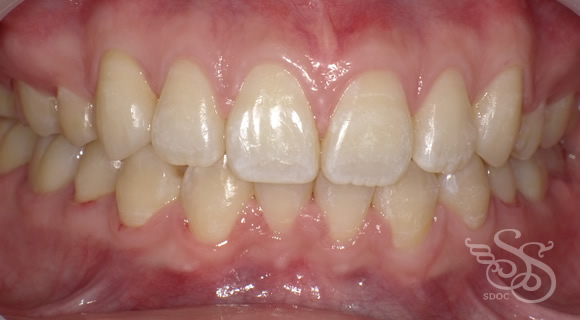

正面:術前

正面:術後

開口(オープンバイト・前歯が閉じない)